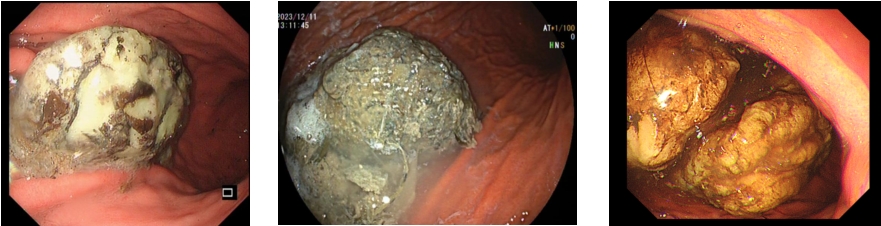

胃镜下胃石的照片

是由于经口摄入了某些食物、异物或药物,在胃内既不能消化又不能及时排出,从而凝结形成的聚合物。胃石多为圆形及椭圆形,可大可小,如鸡蛋或土豆大小结石均很常见。

常用检查方法包括电子胃镜、上腹部CT、B超等。其中,胃镜可直视观察胃内结石的形态、性状及胃黏膜情况。